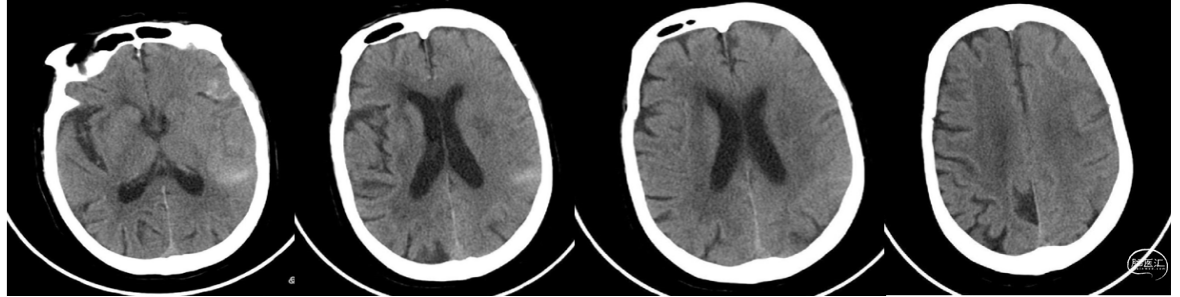

术后12小时患者意识清楚,言语含糊,右侧肢体肌力4级。复查CT:左侧大脑中动脉区域侧裂少量造影外渗。无出血,脑沟略平坦,中线正常。继续脱水脑保护治疗。